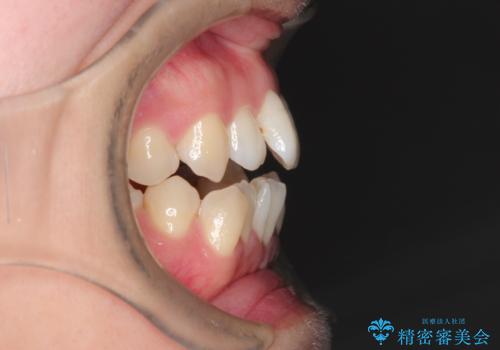

- 前歯がガタガタなのと、前歯でものが噛めないことを主訴に来院されました。

前歯の叢生があり、上下の前歯が接触していない開咬という状態でした。

左側の上下の前から4番目の歯を抜歯して、矯正することとしました。